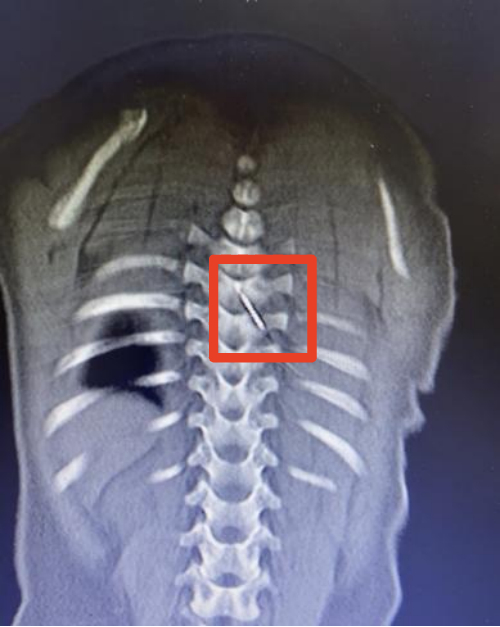

12月5日深夜,仅9个月大的男婴琪琪(化名)被紧急送往国家儿童区域医疗中心、安徽省儿童医院救治。原来,一根长约3厘米的缝衣针裹在被子里,竟在孩子睡觉时悄悄“钻”进了他的后背,并随着身体移动不断深入,最终扎入了琪琪的脊柱内,紧贴脊髓的危险区域。

“这是我见过最危险的异物损伤之一。”该院儿童骨科主任医师张亚鹏说,“针的位置极其刁钻,周围密布重要血管和神经,就像在布满电线的墙壁里取一根针。”

凌晨2点,手术室亮起了无影灯。该院儿童骨科、麻醉与围术期医学科、儿童重症医学科、影像科多学科专家组成的抢救团队严阵以待。通过三维CT影像,医生们精确还原了针的走行路径和周围解剖结构。